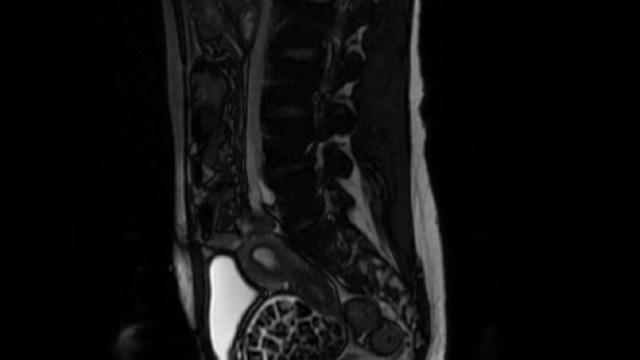

Hastasının durumuna yönelik konuşan Üroloji Uzmanı Doç. Dr. Erkan Erkan, "Hastamızın 2004 yılında doğduğunu ardından doğar doğmaz ekstrofi vezika dediğimiz 50 binde bir görülen bir anomaliden dolayı art arda ameliyatlar geçirdiğini öğrendik. 10 yaşında yine bir ameliyat geçirmişti, gerekli görüntüleme ve tetkiklerimizi yaptırdık. Normalde mesanesinin olması gereken yerin hemen arka kısmında taşlarla dolu bir kese olduğunu gördük, bunun üzerine ek görüntülemeler; MR çektirdik. Hastamız çelişkili açıklamalar almıştı, kendi radyolojik kliniğimiz ve edindiğimiz konsültasyonlarda taşların mesanede değil vajinal boşlukta oluştuğunu düşündük, bir planlama yaptık. Kadın doğum hocamızın da çabasıyla taşları tamamen temizledik ardından ileride normal bir hayat sürmesi bakımından oraya plastik cerrahi yaptık. 287 adet taş çıkardık, pratikte gerçekten görünce çok şaşırdık çünkü bu aynı zamanda literatürde çok nadir görülen bir olay. Biz ameliyata hazırlanırken de teorik olarak biraz araştırdık. Literatürde gördüğümüz kadarıyla buna benzer bu tanıma uyan bir vaka vardı. Literatürde sanırım yayınlanmış 2’nci vaka olacak. Farkındalık çok önemli, bilinçli bir hastamız vardı. Doğumsal anomaliyle doğan çocuklarımızda ileride bunlara bağlı bazı sıkıntılar çıkabileceğinin öngörülmesi lazım. İlgili tedavilerini alsalar bile düzenli takiplere gelmeleri gerekiyor. İleride eğer dikkat etmezse ki zannetmiyorum, tekrarlayabilir. Bu rahatsızlık ekstrofi vezikal epispadias durumu çok nadir bir durum" dedi.

Genç kızın uzun süredir devam eden karın ağrısı olduğunu söyleyerek sözlerine başlayan Jinekolojik Onkoloji Uzmanı Op. Dr. Emin Erhan Dönmez, "Mesane taşları olduğu düşünülerek daha büyük bir hastaneye refere edilmiş. Aramızda mini bir konsey yaparak muayene ettik. Vajen bir hazne görevi görerek orada durağan bir idrar, uzun süre beklediği için idrar içindeki minerallerde çökerek taşlar oluşmuş. Mesanedeki idrarın vajene akmış olabileceği ve vajende göllenen idrar nedeniyle taşların burada oluşacağını düşündük, ameliyatımızı planladık. Ameliyata tanı amaçlı girmiştik, sistoskopi (Mesane gibi idrar yollarını kapsayan kısımlardaki rahatsızlıkların teşhis ve tedavisinde kullanılan endoskopik bir yöntem) dediğimiz ameliyatı Erkan Hocam ile birlikte gerçekleştirdik. Önce mesaneyi bir görüntüledik, mesane tabanına yaklaşık 2-3 cm’lik bir alandan vajene fistülize olduğunu gördük. Mesaneden vajene geçtiğimiz esnada tüm vajenin taşlarla dolu olduğunu gördük. Tanı amacıyla girdiğimiz ameliyatta her şey de olağan gittiği için tedaviye geçtik. Taşların çıkabileceği kadar bir genişlik sağladık. Daha sonra yaklaşık en büyüğü 2,5 cm boyutlarında olan, irili ufaklı 287 tane taşı ameliyat esnasında çıkarmış olduk. Taşların tekrarlamaması için idrarın göllenmemesi, en azından dışarıya rahatça boşalabilmesi için vajinal rekonstrüksiyonu sağladık. Ameliyatta da herhangi bir problem yaşamadık. Literatürü Erkan Hocam ile birlikte değerlendirmiştik. Primer olarak vajende birikmiş olan bu kadar çok sayıda taşla ilgili bir makale görmedik, rastlamadık" dedi.

Hastalık ve tanı sürecine ilişkin bilgi veren Op. Dr. Dönmez sözlerine şöyle devam etti: "Konjental anomali, bunu gebelik esnasında yapmış olduğumuz ultrasongrafi muayenelerinde saptayabiliyoruz. Normalde mesanede idrar birikmesi gerekirken biz ultrasonda bu bebeklerin mesanesinde birikmediğini görüyoruz. Oradan tanıya gidebiliyoruz. Önemli olan burada tanıyı koyduktan sonra bu hastaların 3’üncü düzey, multidisipliner bir hastanede doğum yapmasını sağlamak. Doğumdan sonra en kısa sürede mesane rekonstrüksiyonunun multidisipliner ekiplerle gerçekleştirilmesini sağlamak çünkü mesane direkt karın dışına açıldığı için enfeksiyona açık bir ortam oluşuyor. Bebeğin hayatını tehdit edecek ciddi enfeksiyonlar gelişebiliyor. Anomalilerin durumuna göre bu hastalar bir sıra ameliyat geçirerek sağlıklı bir şekilde hayatlarına devam edebiliyor. Hastamızı muayenelerine, kontrollerine çağıracağız. Biz de o kadar taş beklemiyorduk, maksimum 100-110 kadar bir taş vardır diye bir düşüncemiz vardı, sayalım dedik. 287 taş da bizi ameliyat esnasında heyecanlandırmıştı. Saydıktan sonra bu bilgiyi hastamız ve ailesiyle paylaştık. Onlar da şaşkınlık halindeydi, böbrek taşını düşüren bir kişiyle konuştuğunuz zaman bir taşın bile ne kadar zor bir şekilde düştüğünü size tarif edecektir. Taşların uzun yıllar boyunca yavaş yavaş oluştuğunu düşünüyoruz."